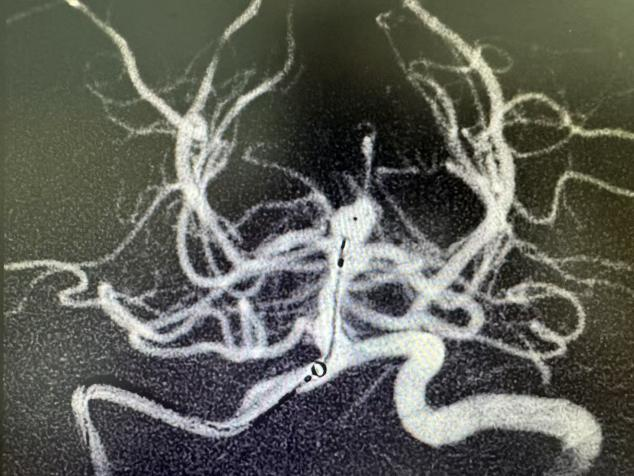

(DSA造影显示基底动脉末端动脉瘤)

2025年8月,64 岁的陈姨(化名)突发剧烈头痛,随后陷入昏迷,家人紧急将其送往中山市博爱医院,距发病已过去2小时。急诊头部CT检查显示,她颅内有大量蛛网膜下腔出血,且已破入脑室——这正是脑动脉瘤破裂的典型表现,病死率和致残率极高。血管内介入治疗是此类急症的主要救治手段,中山市博爱医院神经外科团队以及介入科迅速响应,精准植入Web扰流装置封堵动脉瘤,随后为其实施脑室外引流术,如今陈姨恢复良好,未留下神经功能障碍。

弹簧圈栓塞技术在脑动脉瘤治疗中应用已久,而 Web 扰流装置作为新型治疗方式,正在中山市博爱医院神经外科团队等专业力量的运用下,以显著优势守护患者生命,陈姨的康复就是有力证明。